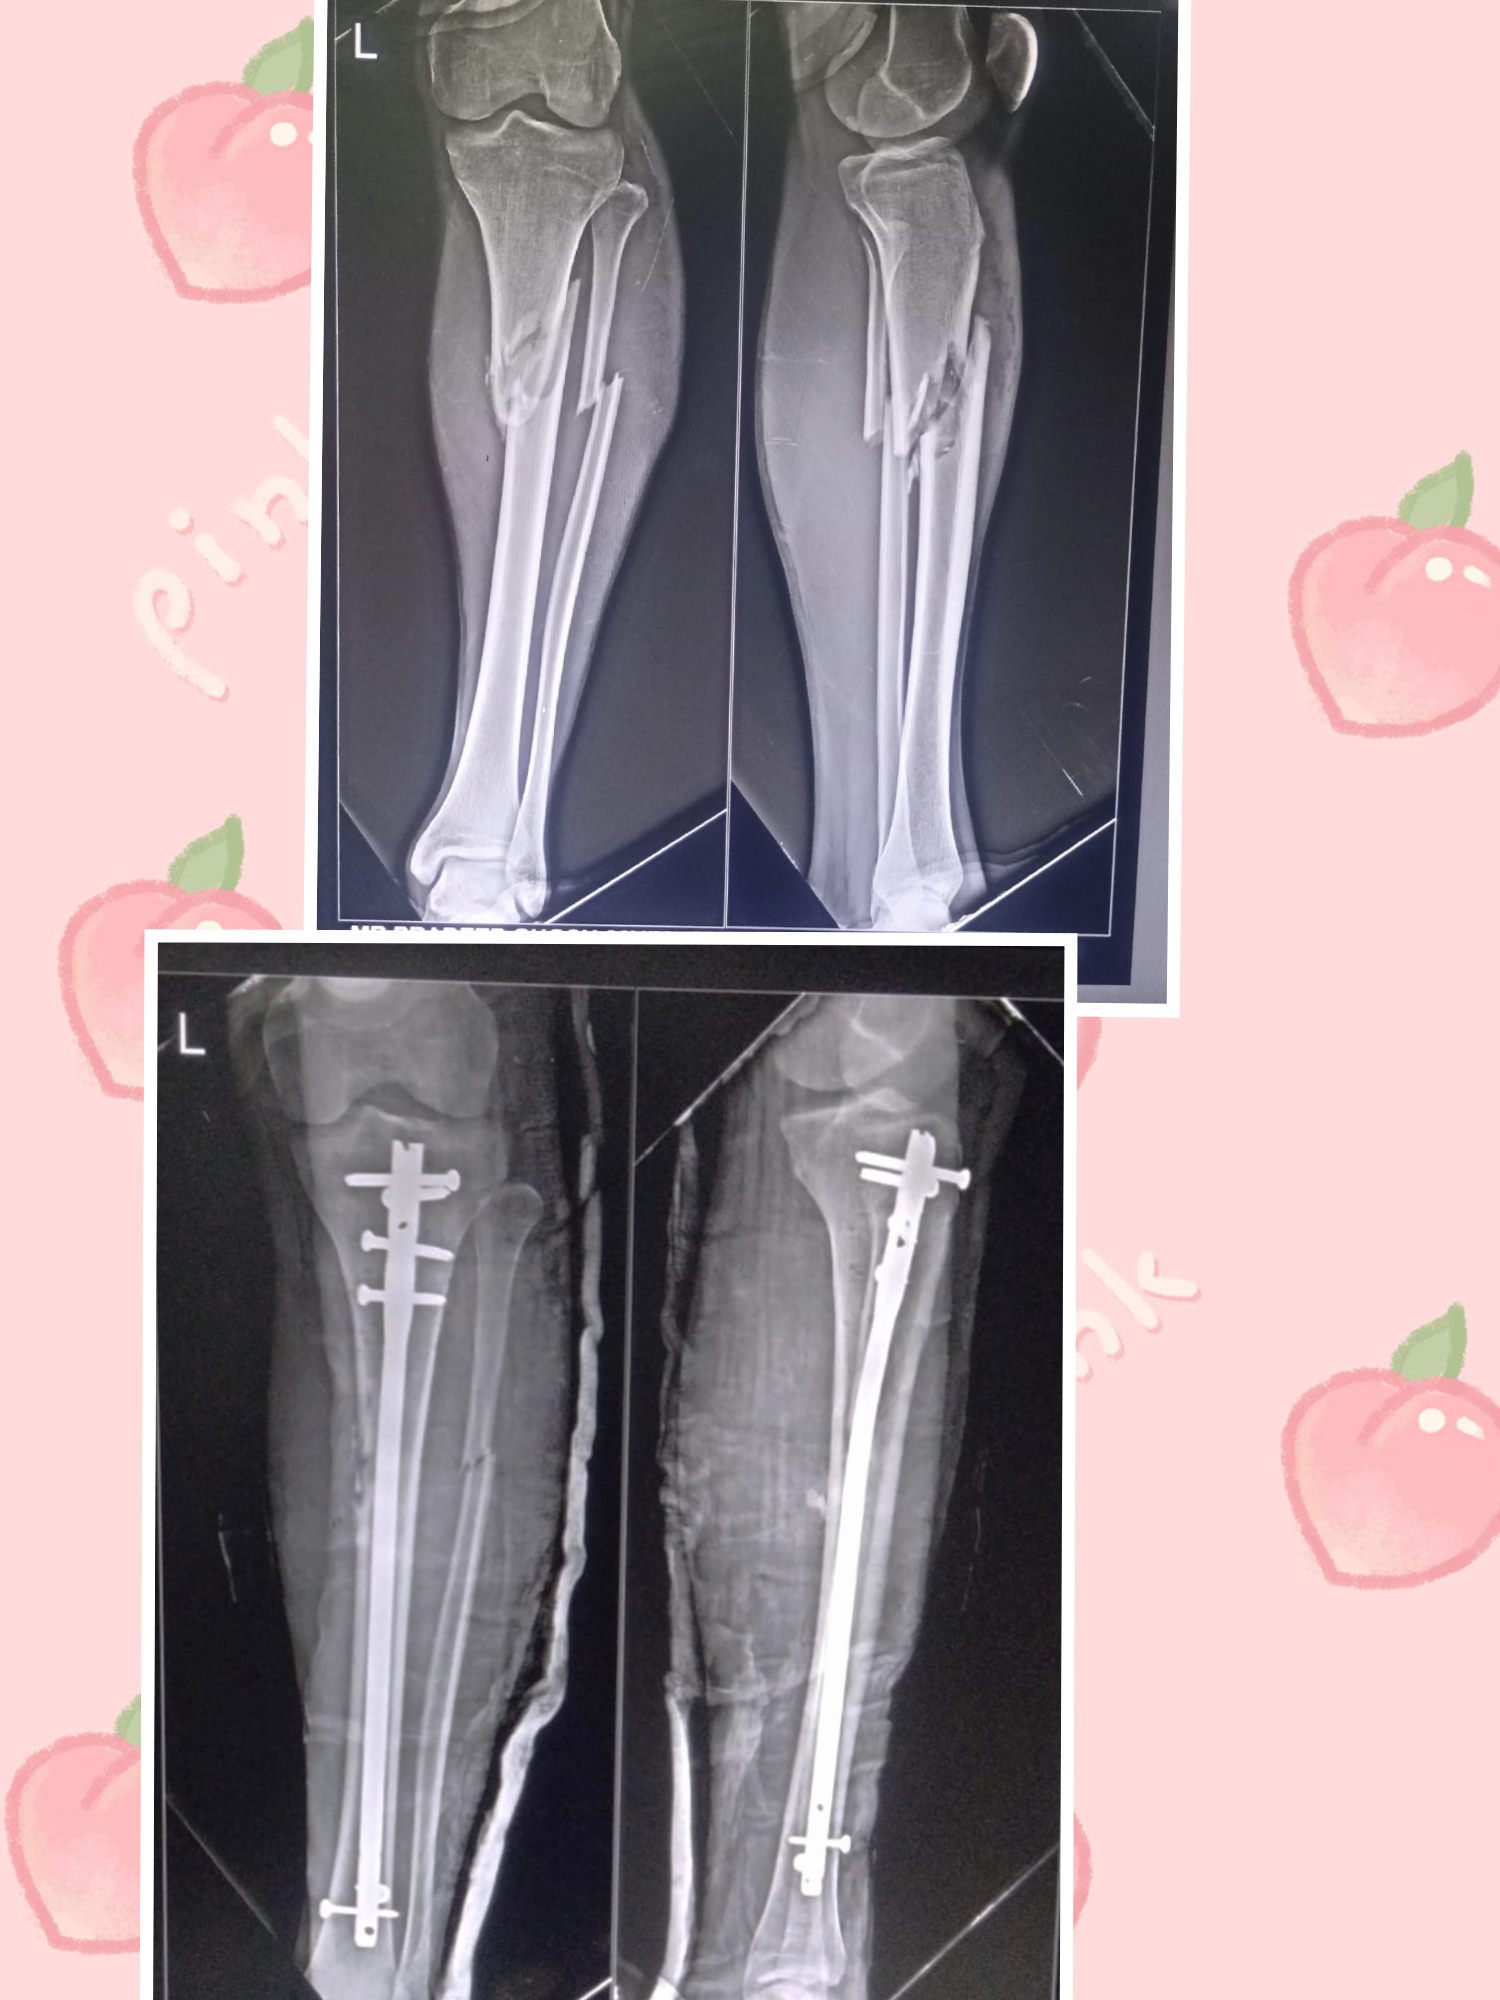

20 year old male with road traffic accident sustained left leg injury with closed fracture of left tibia fibula with no neurovascular deficit. Patient was operated with open reduction and internal fixation with suprapatellar expert tibia nail. Post-operatively patient mobilized on walker.